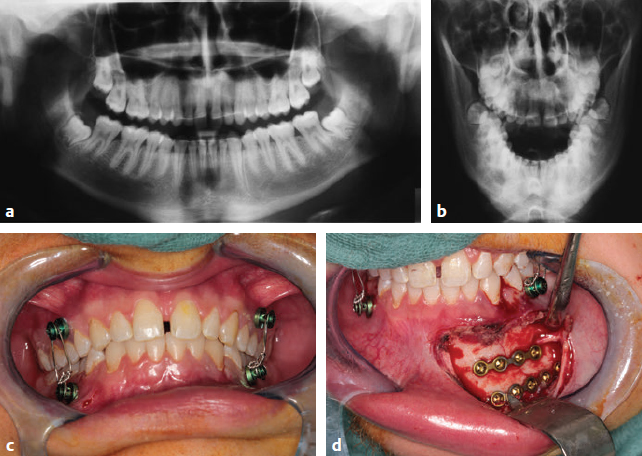

CHAPTER The long-term outcome after jaw fractures depends not only on the type of fracture and the precise restoration of the broken bone, but also on the integrity of all anatomic structures neighboring the fracture. Choosing the appropriate surgical approach is an additional key factor for avoiding complications. This chapter focuses on the management of upper and lower jaw fractures. Direct and indirect forces to the lower and upper jaw result in fractures. Several low-resistant anatomic locations with thinned bone are prone to fractures. Typical fractures (Fig. 47.1) of the maxilla include the so-called Le Fort I fracture, in which the maxilla breaks off the midface (A in Fig. 47.1), and sagittal fractures (see B in Fig. 47.1), which involve transverse expansion of the upper jaw. With regard to the mandibular bone, the parasymphyseal (see C in Fig. 47.1) and the angle (see D in Fig. 47.1) regions are prone to fractures. The extended root of the lower canine and the foramen of the mental nerve are responsible for parasymphyseal fractures, whereas retained wisdom teeth are a determinant in angle fractures. The thin condylar neck (see E in Fig. 47.1) including the condylar head (see F in Fig. 47.1) is another fragile region of the mandible. High-velocity trauma leads to comminuted fractures (see G in Fig. 47.1). In particular, the uncompleted median symphysis in children is highly vulnerable. Pathologic conditions of the bone such as osteomyelitis or osteonecrosis (see H in Fig. 47.1) increase the risk of fractures, as does an edentulous, highly atrophied body of the mandible1,2 (see I in Fig. 47.1). The anatomical complex of the upper and lower jaw is functionally involved in clenching and speaking, but also plays a significant role for facial aesthetics. Restoration of painless unlimited mouth opening, laterotrusion, and protrusion is one of the main targets after jaw fracture. Perfect occlusion should be recovered in dentate patients, and the harmonic red-white aesthetics of teeth and gingiva should be reestablished. As a basis for later prosthetic rehabilitation, the accurate positioning of the maxilla and mandible in the vertical, transversal, and sagittal dimension is always necessary.3 Undesirable results after treatment of jaw fractures arise, in most cases, because of deficient clinical and radiological diagnostics and insufficient treatment planning.4 To a lesser extent, poor outcome results from the failure of the patient to cooperate or from a lack of postoperative care. Open reduction and internal fixation (ORIF) is the basic reconstructive principle in nearly all types of jaw fractures. Since their development in the 1970s, titanium miniplates represent the osteosynthesis material of first choice for the maxilla and for the mandible.5 Fundamental publications have described the buttresses of the facial bones.6 Most postoperative complications can be avoided when the rules of miniplating along the natural strains of the bones are strictly observed. For exceptional cases in which bone has been sheared off, lag screws might be a therapeutic alternative. Particular attention must be paid to jaw fractures in childhood. The jaw bones of children have a high potential for bone remodeling. Reconstructive principles have to be modified; closed reduction is a sufficient therapy in many cases.7 If ORIF is conducted, plate removal must be performed much earlier. Fig. 47.1 Types of jaw fractures (blue, maxillary fractures; red, mandibular fractures). A, Le Fort I fracture. B, Sagittal upper jaw fracture. C, Parasymphyseal fracture. D, Angle fracture. E, Fracture of the condylar process. F, Fracture of the condylar head. G, Comminuted fracture. H , Pathologic fracture (osteomyelitis, osteoradionecrosis, medication-related osteonecrosis). I, Fracture of the atrophic jaw. This chapter concentrates on the most challenging types of jaw fractures, because of their high potential of therapeutic failure. After the breaking off of the midface, the pterygoid muscles pull the fractured upper jaw into a dorsal position. Nonocclusion, open bite, and nasal airway restriction result. In the long term, the facial profile changes by the retral position of the maxilla and the subnasal region. The patient presents with pseudoprogernia. When reducing the fracture, retral positioning of the maxilla must be avoided, and particular attention should be paid to the exact positioning of the maxilla. A posteriorly impacted maxilla must be pulled forward. Significantly delayed cases should be reduced with Rowe’s maxillary disimpaction forceps. The two-pronged instrument grasps the maxilla with a palatal blade and a blade positioned in the nasal cavity. After reduction, meticulous mandibulomaxillary fixation is necessary to secure the occlusal relationship until osteosynthesis with miniplates is performed. After ossification of the malpositioned maxilla, a secondary correction must be carried out. Preoperative planning is therefore indispensable. First, plaster models from the maxilla and mandible are made, a checkbite is performed, and the positions of the maxilla with respect to the temporomandibular joint (TMJ) and the cranial base are determined with a face-bow. To imitate the position of the jaws and the mandibular movements, upper- and lower-jaw casts are positioned correctly in an adjustable articulator. With respect to the posttraumatic and intended facial profile, occlusion and aesthetics model osteotomy is performed on the casts. The exact movement of the maxilla in three dimensions is ascertained and marked on the model. Occlusal splints, namely a starting splint and a postosteotomy splint, are made on the basis of the model operation. These splints are fixed between the maxilla and the mandible during the Le Fort I osteotomy. Summary Box Unfavorable Results and Complications Associated with Fractured Jaw Repair Maxilla Fractures • Le Fort I fractures – Open bite – Nasal airway restriction • Sagittal fractures Mandibular Fractures • Plate exposure • Injury to mental nerve • Injury to root of lower canine • Infection Condylar Process Fractures • Malocclusion • Condylar absorption • Arterial hemorrhage • Nonocclusion • Reduced mouth opening • Limited mandibular movement • Osteonecrosis • Scarring • Facial nerve paralysis • Parotid fistulae • Infection • Scarring stenosis of the auditory canal • Dislocation of osteosynthesis material Comminuted Fractures • Discontinuity of the bone • Infection (abscesses, cellulitis, osteomyelitis) • Nonunion and malocclusion • Nerve injury Pathologic Fractures • Class A • Class B • Class C Atrophic Jaw Fractures • Complication in bone healing • Stability loss of mandible • Extraoral plate exposure • Intraoral plate exposure • Fractured osteosynthesis material Childhood Jaw Fractures • Facial asymmetry • Malocclusion/open bite • Joint ankylosis Secondary correction of maxilla malpositioning can also be carried out by virtual planning of a Le Fort I osteotomy. Once a computed tomography (CT) scan of the middle and lower face is obtained, the data is prepared with a special software to gain a virtual three-dimensional model. The required movement of the maxilla can be simulated, and individual cutting guides and osteosynthesis material for the Le Fort I osteotomy can be produced by industrial partners within a few days.8 Sagittal fractures are accompanied by transverse malposition, resulting in transverse expansion of the maxilla and nonocclusion. In some cases, sagittal fractures with extensive dislocation cause lacerations of the palatal soft tissues with oronasal communication. The alveolar process is often tilted, which makes it difficult to achieve a sufficient occlusion solely by maxillomandibular wiring. The fabrication of an individual acrylic palatal plate might be indicated for better stabilization of the palatal vault. After this pretreatment, osteosynthesis is carried out with miniplates being placed on the frontal part of the maxilla. Additional problems might arise from laceration of the palatal gingiva. Primary tension-free closure is challenging, because mobilization of the palatal soft tissue is nearly impossible. As an unfavorable result, a persistent oronasal fistula might occur. Closure of such fistulas is hampered by scarring. The use of a pedicled palatine flap and the mobilization of the buccal fat pad are therapies of the first choice for oronasal fistula closure. Techniques for the closure of recurrent or extended oronasal fistulas are associated with much more donor site morbidity and include the tongue flap or a radial forearm flap (Fig. 47.2). Fig. 47.2 Persistent oronasal fistula after sagittal fracture of the maxilla. (a) After repeated trials of primary closure. (b) Final closure with a tongue flap. The treatment of these types of mandibular fractures is based on the miniplating techniques developed by the group led by Champy9 in the 1970s. With the exception of the angle region, two monocortical fixed miniplates (four-hole or six-hole) are placed on the buccal surface of the mandible. Whereas one plate is fixed below the dental roots, the other one is fixed at the mandibular base to neutralize moments of torsion (Fig. 47.3). In the angle region, the muscle sling of the masseter and medial pterygoid muscles compresses the strains of the mandibular base. Therefore placement of a single plate running from the postmolar oblique line to the buccal molar region is adequate. If the principles of miniplate osteosynthesis are fulfilled, complications are rare. Unfavorable results such as plate exposure can arise when the intraoral incision is placed directly over the fixed titanium plates. Postoperative smoking and poor oral hygiene are cofactors that increase the risk of plate exposure. Particular attention must be paid to the mental nerve and the root of the lower canine in parasymphyseal fractures. Injuries of these anatomic structures from incorrect placement of screws and miniplates can easily be avoided. If plate exposure occurs, further infection of the region must be prevented. Strict oral hygiene must be maintained, including antiseptic mouthwashes, and the patient must be seen weekly in the maxillofacial outpatient clinic. Osteosynthesis material removal is delayed to at least 2 months to allow bony consolidation to be completed. The treatment of condylar fractures is a controversial topic. During the past decade, much effort has been made to improve the outcome of condylar fractures, but after critical consideration, many of the “new techniques” have been abandoned as fast as they have emerged. Taking all conflicting points into consideration, the surgeon has the choice of treating all cases conservatively or performing ORIF on the other. Various complications arise after the fracture and treatment of the condylar neck and head. Functional, aesthetic, and neurosensory deficits are common.10 Malocclusion, reduced mouth opening, and limited mandibular movement are often associated with the pterygoid lateral muscle pulling at the fractured and nonfractured fragments.1 Malocclusion also results because of the dislocation of the condylar process and subsequent reduction of ramus height. Osteonecrosis of the condyle might be an unfavorable result of traumatic or iatrogenic disruption of the blood supply to the small broken fragment. Surgery-associated problems include unfavorable scarring and facial nerve paralysis, mostly of the marginal mandibular branch, after use of an extraoral approach for ORIF. In addition, parotid fistulas and sequential infections have been described after a transcutaneous transparotid approach to the fractured condylar process. Scarring and subsequent stenosis of the auditory canal is also a problem that arises after ORIF of condylar head fractures through a retroauricular approach.10 Fig 47.3 Management of mandibular fractures. (a,b) Radiologic diagnostics are performed in two planes with panoramic and mandible posteroanterior radiographs. (c) Maxillomandibular fixation with screws and wires. (d) Open reduction and internal fixation with miniplates considering the anatomy. The technique of the anatomic repositioning of the condylar head fragments with trapezoid plates and successive definitive screw fixation to the stable mandible can result in the dislocation of osteosynthesis material. A via falsa of the inserted screw with significant harm to surrounding structures can occur. Although bleeding from the external auditory meatus is common after posterior dislocation of the condylar head, the penetration of the fractured condyle to the middle cranial fossa might, in rare cases, result in life-threatening infections and complications.11 Modern diagnostics of condylar process fractures should not rely only on clinical parameters and plain radiographs such as panoramic and mandible posteroanterior radiography. Mandible posteroanterior radiographs might provide a hint to the grade of dislocation of the fractured segment. For an exact classification of the segment and determination of the treatment concept, a further investigation with a three-dimensional technique (computed tomography [CT], cone beam computed tomography [CBCT]) is required. Exact and reliable control of the post-therapeutic effect on the posttraumatic state can only be achieved by CT and CBCT. The condylar fracture classifications of Spiessl et al.12 and Loukota et al.13 are helpful in determining whether the fracture should be done operatively and which surgical approach is the most suitable. The classification by Spiessl et al.12 (Fig. 47.4) suggests that ORIF is definitely indicated for healthy adults with type IV and type V fractures (Box 47.1). Luxation of the condylar head out of the TMJ socket is associated with a massive loss of vertical height and nonocclusion and, in bilateral luxations, with the development of an iatrogenic malpositioning of an adjusting screw and retral position of the mandible. Therefore the repositioning of the condylar process and the securing of this position by osteosynthesis is essential (Fig. 47.5a). The classification by Spiessl et al.12 does not differentiate between the severity of dislocation in type II and type III fractures. Dislocated fractures with a deviation of the condylar process of less than 30 degrees can be treated by maxillomandibular fixation and early functional therapy (Fig. 47.5b). This suggestion includes, in particular, unilateral cases, cases without loss of vertical height, and posttraumatic normo-occlusion. Wired arch bars for maxillomandibular fixation should be used in all cases with slight dislocation. In type I and type VI fractures without dislocation, I recommend four bone screws be placed between the roots of the canines and the first premolar carefully avoiding violation of the teeth or their roots. During the first postoperative week, maxillomandibular fixation must be ensured by rigid elastics (type III and IV), after which soft elastics (type VI to VIII) are indicated for another 3 weeks. Soft elastics should allow mouth opening and alleviate functional therapy. Rigid maxillomandibular fixation should be limited to 2 weeks, especially in younger patients, to prevent bony ankylosis of the TMJ. Radiographic observations after maxillomandibular fixation are essential to detect spontaneous dislocation during manipulation at an early stage. If this occurs, secondary ORIF is necessary. Fig. 47.4 Fracture types of the mandibular condyle as classified by Spiessl et al, with indications for open reduction and internal fixation marked in pink. Open reduction and internal fixation (ORIF) is recommended in mandibular condyle fractures with the following characteristics: • Luxated condylar fragment • Dislocation of the condyle of more than 30 degrees • Massive loss of vertical height Exceptions to the algorithm can/must be: • Posttraumatic normo-occlusion • Multimorbid patients with potential life-threatening risk during narcosis • Children younger than 12 years with a high potential of condylar remodeling • ORIF is indicated (even in slight dislocations) in*: Fig. 47.5 Indications for open reduction and internal fixation in fractures of the mandibular condyle. (a) Loss of vertical ramus height. (b) Dislocation of the condylar fragment of more than 30 degrees. Because of the earlier mentioned risks of ORIF in condylar head fractures (condylar head resorption, stenosis of the auditory canal, facial paralysis, and dislocation of osteosynthesis material), I recommend closed reduction with functional therapy in such cases. If primary therapy results in nonocclusion, I recommend orthodontic therapy followed by secondary orthognathic surgery after several months. Loss of vertical height can be corrected by vertical ramus osteotomy. Loukota et al.13 published a new classification of condylar fractures in 2005. They defined an anatomic A-line that crosses the most inferior point of the semilunar incisure of the mandible. The A-line starts as a perpendicular line to a tangent touching the most posterior points of the ramus and the condylar head13 (Fig. 47.6). To define the surgical approach, The A-line is an extremely helpful tool for determining the surgical approach (Fig 47.7). Although numerous approaches to the mandibular condyle have been developed, I rely on three main approaches depending on the anatomic position of the fracture with regard to the A-line. Condylar base fractures located inferior to the A-line are reduced via an intraoral approach (Fig. 47.7a), condylar base fractures running through the A-line are treated by a retromandibular approach (Fig. 47.7b), and condylar neck fractures superior to the A-line are reduced via a rhytidectomy-transparotid approach (Fig. 47.7c). The latter approach can be extended as a preauricular incision superior to the temporal region if the condylar head region must be reached (Fig. 47.7d). Fig. 47.6 Anatomic relationship in fractures of the condylar process. The A-line is a perpendicular line to the mandibular ramus tangent running through the inferior part of the incisure of the mandible. Fig. 47.7 Recommendation for the surgical approach with respect to the anatomic location of the condylar fracture. When approaching a condylar base fracture transorally, the overview to the backside of the ascending ramus is reduced. Nevertheless, correct repositioning of the fragments is essential, and hooks and retractors are helpful. However, iatrogenic injuries caused by pulling forces to the retromandibular vein and the accompanying marginal mandibular branch of the facial nerve must be avoided. In the early 2000s, the technique of endoscopic revision of condylar fractures via a transoral approach was commonly cited in the literature.14,15 However, four main complications are common with this technique: 1. Arterial hemorrhage 2. Facial nerve injury 3. Nonunion 4. Partial condylar reabsorption After critical analysis of their results, Arcuri et al.16 believe that this is not an ideal approach for a subcondylar fracture but might be an alternative procedure in selected cases. With the retromandibular approach (Fig. 47.8), the surgeon must pay particular attention not to injure the marginal mandibular branch of the facial nerve. Therefore it is useful to prepare the retromandibular vein after skin incision (see Fig. 47.8b) and to visualize the nerve (see Fig. 47.8c). The periosteum is cut anterior to the marginal mandibular branch, and the fracture is exposed (see Fig. 47.8d). The vestibular surface and the posterior rim of the ramus are prepared to obtain a complete overview of the fractured bone. Distraction of the anterior mandible is commonly necessary to reduce the dislocated fragments anatomically. The algorithm recommends a rhytidectomy anteroparotid-transparotid approach for condylar neck fractures. To prevent complications involving the facial nerve, a strictly subcutaneous preparation is necessary after skin incision. The capsula of the parotid gland is either saved when carrying out an anteroparotid approach or dissected horizontally when a transparotid approach is used. When the anteroparotid approach is used, dissection is carried out subcutaneously until the masseter muscle is reached in front of the gland and until the overlying nerve branches have become obvious. Attention must be paid to leaving the excretory duct of the gland intact. The parotid gland is then retracted backward, and the masseter muscle is cut horizontally between the two nerve branches. The fracture can be exposed and anatomically reduced. After osteosynthesis, meticulous control of hemorrhage is essential. Reconnection of the masseter muscle with 3–0 or 4–0 resorbable suture is also mandatory to restore its function. A suction drain is inserted before skin closure to prevent hematoma and hematoma-induced facial nerve palsy. Cutaneous closure is performed with 4–0 or 5–0 nonresorbable sutures to prevent scarring. The transparotid approach involves cutting the parotid capsule parallel to the nerve branches. Nerve branches must be detected by an electrostimulation device. The incision of the capsule is marked with sutures to visualize it later. After dissection of the gland and the masseter muscle, a more direct view of the fracture becomes visible than via the anteroparotid approach. However, the masseter muscle must be reattached and the capsule closed tightly after osteosynthesis. Tight capsular closure is essential to prevent salivary fistulas that might occur in about 1% of the cases.17 Treatment of salivary fistulas or sialoceles can be either carried out surgically by reevaluation of the parotid or conservatively. Acceptable conservative regimens include, as a first step, compression bandaging and drainage and, as a second step, the insertion of a feeding tube for 8 days and additional administration of antisialogogs.18 A single injection of botulinum toxin type A to the parotid gland has also been described as a promising therapy.19 Fig. 47.8 The retromandibular approach for a condylar base fracture. (a) Preoperative marking of the anatomic landmarks and incision. (b) Preparation of the retromandibular vein. (c) Exposure of the marginal mandibular branch of the facial nerve anterior to the retromandibular vein. (d) Visualization of the fracture. Fig. 47.9 Fatigue of osteosynthesis material and consecutive plate fractures in both condylar regions. Fig. 47.10 Correct angle of 30 degrees between two 2-mm miniplates in a condylar base fracture. (a) Intraoperative view after open reduction and internal fixation. (b) Postoperative control using cone beam computed tomography. Osteosynthesis is one of the most important, if not the key procedure in the surgical treatment of condylar fractures. Many osteosynthesis systems are available. Special osteosynthesis plates and screws have been developed to fulfill the requirements of the mandibular condyle (e.g., lag screws, triangular plates, locking plates, resorbable plates). The system must fit the usually small condylar fragments, be adaptable via the restricted approach, and withstand bite forces (Fig. 47.9). The correct placement of the osteosynthesis material into the condyle process and the mandible has been the matter of myriad investigations. Tensile and compression forces to the mandible and its condylar process have been measured by photoelastic analysis, three-dimensional biomechanical simulation models, and finite element models.20–22 The results of these investigations stress that two-plate fixation with 2-mm four-hole miniplates is superior to all other stabilization techniques.22,23 Meyer and colleagues24 states that “more and more authors advocate the use of two miniplates. The first is placed in the axis of the condylar neck as usual, and the second is placed obliquely under the mandibular notch.”24 In my own experience and in accordance with Meyer,24 two miniplates are needed. After anatomic reduction of the fracture, the first four-hole miniplate is placed in the axial direction of the condylar neck. With gracile condylar necks, particular attention should be paid to ensure that the first plate is placed posteriorly enough for the second to be positioned anteriorly. Monocortical screws of 5 mm or 6 mm are used to fix the plate. After this maneuver, a control of the occlusion is recommended. If the occlusion is correct, the second plate is placed (according to the natural strains) 30 degrees in an anterior direction to the first, and all screws are drilled in (Fig. 47.10). The gold standard for postoperative control is three-dimensional radiographic observation by CT or CBCT. Postoperative radiography is essential, not only for forensic reasons. Exact and detailed documentation of the pretreatment and post-treatment status can be of high value if complications—such as malocclusion; mastication pain; or nearthrosis, pseudarthrosis, or ankylosis—arise. Secondary dislocations of the nonoperated site might occur, especially in bilateral condylar fractures with unilateral conservative treatment. Distraction maneuvers during anatomical reduction can often cause these dislocations. In consequence, secondary corrections with ORIF have to be performed. Comminuted fractures occur after high-velocity trauma or shotgun injuries. They are characterized by bone that is crushed into a number of smaller fragments. For this reason, anatomic repositioning can be extremely difficult. Osteosynthesis is hampered by the lack of fixation options for the small bony segments. Because of the trauma mechanism, comminuted fractures are often associated with remarkable injuries to the neighboring tissues, with lacerations of the gingiva and facial skin or even the loss of soft tissue with subsequent defects. The prevalence of fractured, loosened, or knocked-out teeth in these types of injuries is high. Foreign bodies or bullets penetrate soft tissue and bone. In addition to the difficulties of anatomic repositioning and stabilization of the bony fragments, several complications can arise with this type of fracture: • Discontinuity of bone • Infection, mainly as abscesses, cellulitis, or osteomyelitis because of the following: • Nonunion or malocclusion • Nerve injuries The discontinuity of bone results primarily after traumatic loss of a bone fragment or secondarily because of infection and necrosis of a segment. In extended comminuted fractures, a step-by-step approach is recommended to prevent the previously mentioned complications and unfavorable outcomes. First, wounds are cleansed with polyhexanide 0.4% or Ringer’s lactate solution via a syringe; then the surgeon performs a meticulous search for foreign material and tooth fragments. Foreign material, dental fragments, and teeth with vertical fractures and pulp exposure are removed. Teeth in malposition are manually replaced into their sockets without touching the root region. These teeth are fixed with interdental titanium-composite splints for stabilization. If occlusion is reproducible, maxillomandibular fixation is performed, and intraoral soft tissue is closed if necessary. Thereafter the mandible is (if possible) stabilized in occlusion, and the fracture is manually reduced via an extraoral approach. The separate fragments are first allocated and fixed with miniplates and screws. Small fragments that are impractical to fix are removed to prevent dislocation, infection, and necrosis. Subsequently, a load-bearing reconstruction plate is placed on the mandibular base to maintain the mandibular block, particularly when there is a discontinuity of the bone (Fig. 47.11a–c). If bone segments are missing and no obvious signs of infection (e.g., contamination with foreign material) are apparent, I recommend immediate bone augmentation with autologous transplants from the iliac crest. Preconditions for immediate bone augmentation are that the transplants can be fixed effectively and that sufficient soft tissue closure can be achieved. Intravenous antibiotics (amoxicillin and clavulanic acid) are administered three times daily for 5 days to prevent transplant infection. If the preconditions for primary augmentation are inappropriate, the augmentation is performed in a second operation after wound healing is complete. Massive bone loss requires bone augmentation and jaw reconstruction with microvascular transplants. To counteract the effect of the lack of bone coverage, osteocutaneous grafts are the transplants of choice. Modern three-dimensional planning tools can anticipate the amount of bone loss via CT and design custom-made bony transplants virtually. Corresponding cutting guides for bony osteotomy of the recipient and of the donor site are then manufactured by industrial partners (see Fig. 47.11b–f). As previously mentioned, antibiotic therapy is necessary for 5 to 7 days for comminuted fractures. Bone necrosis resulting from small fragments can be avoided if surgical therapy is carried out as described. Finding and removing bullets and splinters can be challenging; intraoperative navigation is a helpful tool for simplifying the retrieval of foreign materials. Plate exposure and infection typically result from the lack of soft tissue coverage of the bone and osteosynthesis material. Effective cleansing and appropriate care of the exposed plate might prolong the time until removal is necessary. Early removal of plates is possible from 6 weeks after osteosynthesis, often with no compromise to the result. If denuded bone cannot be covered adequately, pedicled soft tissue grafts are harvested to cover the hard tissue. Curettage and planning of bony edges are essential; in complex cases, adjacent teeth are extracted to enhance soft tissue coverage. Nonunion typically results from infection or a lack of bony stabilization. Pseudarthrosis is a possible result. Two strategies are available: 1. If pseudarthrosis is stable and the patient appears satisfied with the situation, no further surgery is recommended. 2. If major mobility occurs between the fragments, restabilization with a taller osteosynthesis plate and a bone graft is indicated.